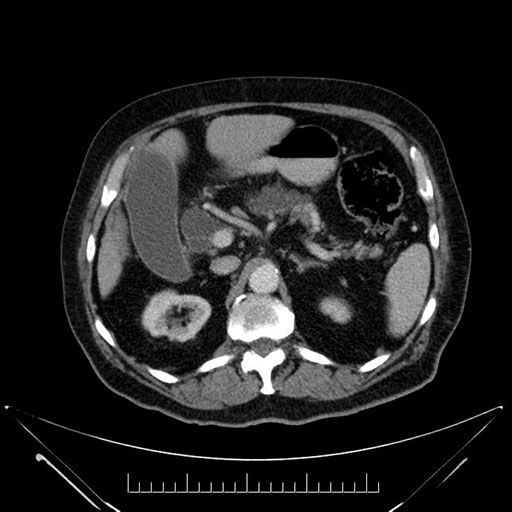

Imaging Analysis

Look through the patient's CT scan to identify any areas of concern for the necessary procedure.

Based on your CT findings, which issue(s) would give reason for "planned slowing down moment(s)" in this case?